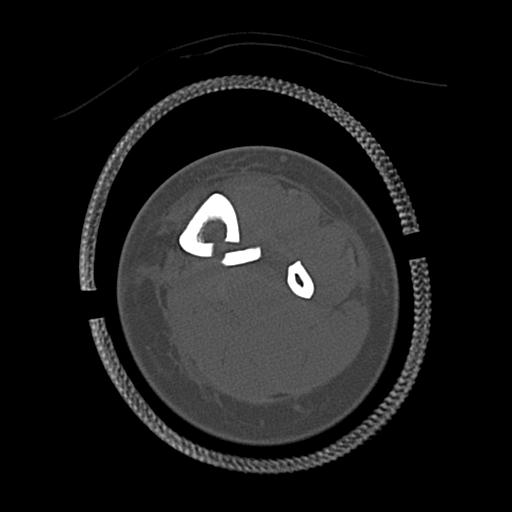

100612 11/25 1/20 右膝 2R 84歳女性 右TKA